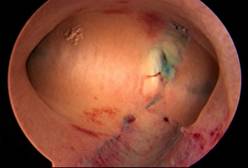

Uterine septum

Trans Cervical Endometrium Resection ( TCRE )